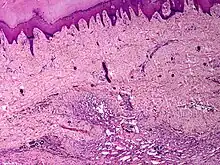

| Skin angiomatosis | |

Histology

It is a vascular malformation wherein blood vessels proliferate along with accompanying mature fat and fibrous tissue, lymphatics and sometimes nerves.[2] They may involve skin, subcutaneous tissue, skeletal muscle and occasionally bone.[2]